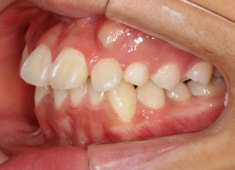

治療開始から11ヶ月後